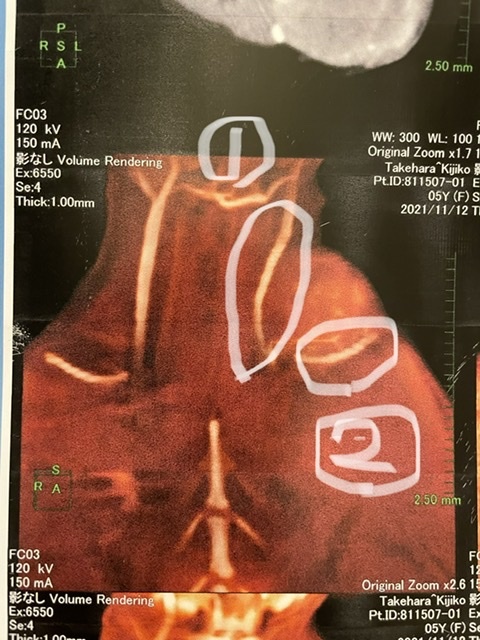

CT画像です。

首付け根に丸い物があるかと思いますがこれがキジコの中にある腫瘍です。

また腫瘍が色んなところに絡んでいるそうです。

別のCT画像ですが①と②と書きましたが

①の部分には頸静脈と腫瘍が絡み、②の部分には鎖骨があります。さらに鎖骨の下には左手の肩があり、今回は腫瘍のみの摘出手術ではなく、再発しないようにその周りにある成長していない腫瘍の細胞も切除することになります。

ただ左手に関しては鎖骨があるため腫瘍の細胞の侵入を鎖骨がガードしてくれている可能性があるため切断をしない方向で進めます。

しかし細胞が侵入していて左手の肩にも腫瘍が出来た場合は左手を犠牲にしないと言われています。

①部分の近くには気管支もあり、腫瘍がさらに大きくなると呼吸にも影響が出てくる可能性があるので出来るだけ早く摘出した方が良い診断されました。